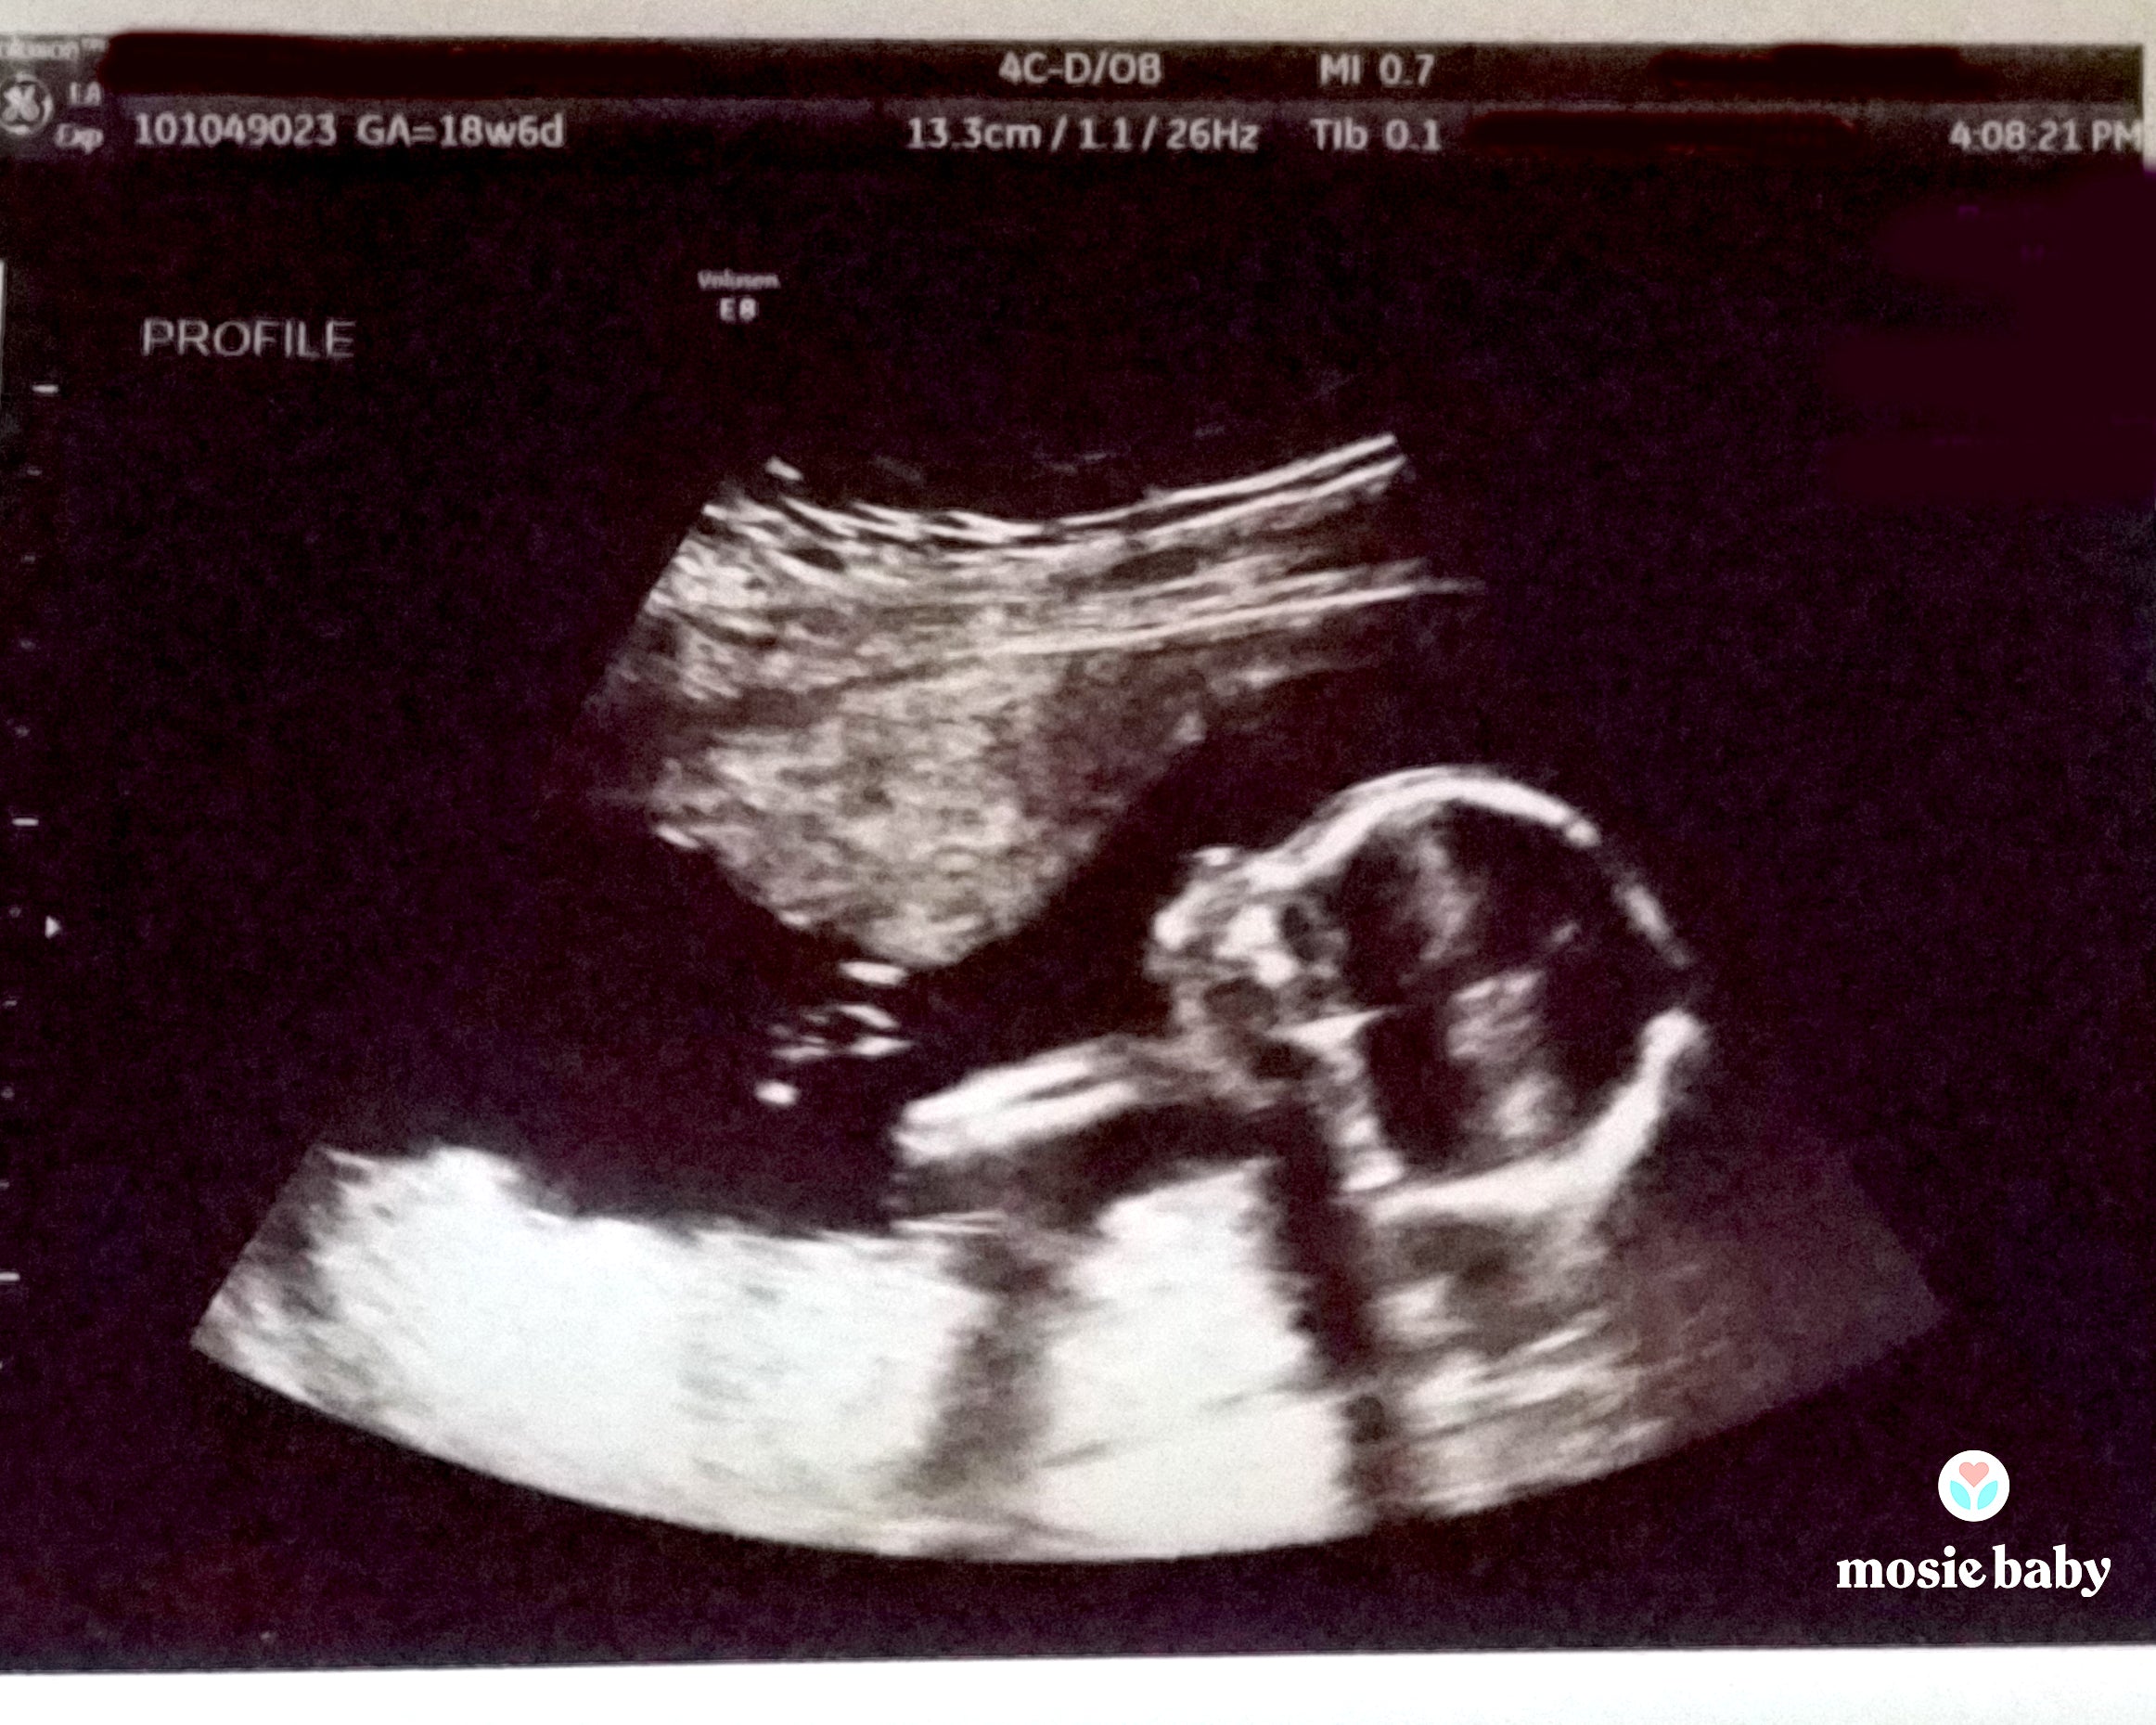

My husband and I decided to begin trying at the beginning of this year. After locating a donor we wanted to use due to my husband not being able to conceive we began research for insemination. After a few months of ovulation tracking and researching at home insemination we came across the Mosie Baby kit. The success stories were extremely positive, and we wanted to have the highest rate of success possible when we attempted to inseminate. We ordered the Mosie Baby kit and made two attempts with the kit and our donor sperm. The kit directions were easy to follow and insemination was easy. Two weeks later we had a confirmed pregnancy. I am now seven months pregnant with our baby girl!!!